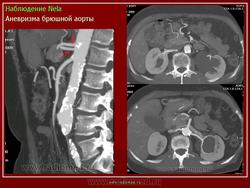

Аневризмы брюшной аорты